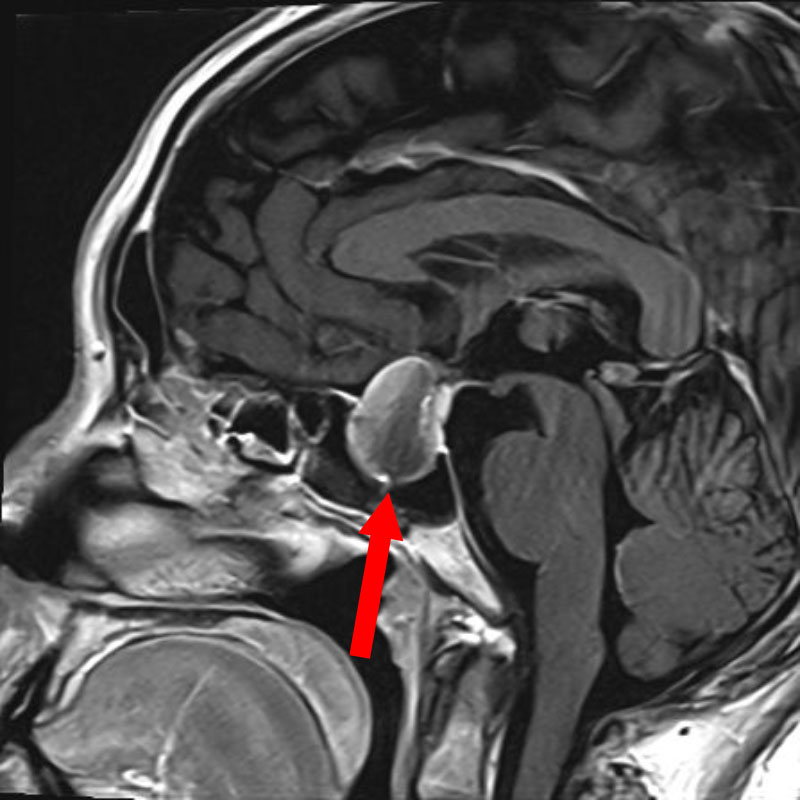

頭蓋咽頭腫

頭蓋内腫瘍摘出術

No.’25_96 手術前1

No.’25_96 手術前2